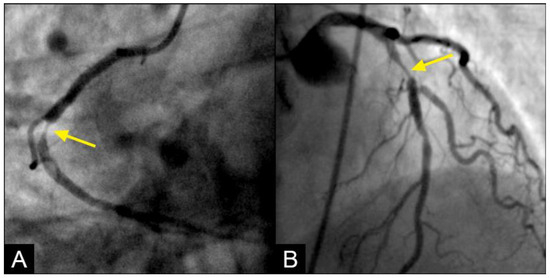

In the right coronary artery (RCA), during diastole, the blood flow could be observed over a black contrast background and identified clearly with well-organized flow and a sharp border, without mixing between blood and contrast, following the apex of the curves. By visual observation, this flow was laminar (Figure 5A–D) (Video S1).

Figure 5.

(A,B) Laminar flow. These four coronary images are in consecutive sequence. (A) This is the angiogram of the right coronary artery (RCA), which is filled with contrast (in black). (B) The blood (in white) is seen well organized with a sharp border and a pointed tip, curving along the apex (yellow arrow). (C,D) The blood (in white) is seen following the apex of the curves (yellow arrow). This is the laminar flow following the curves in a helical fashion.